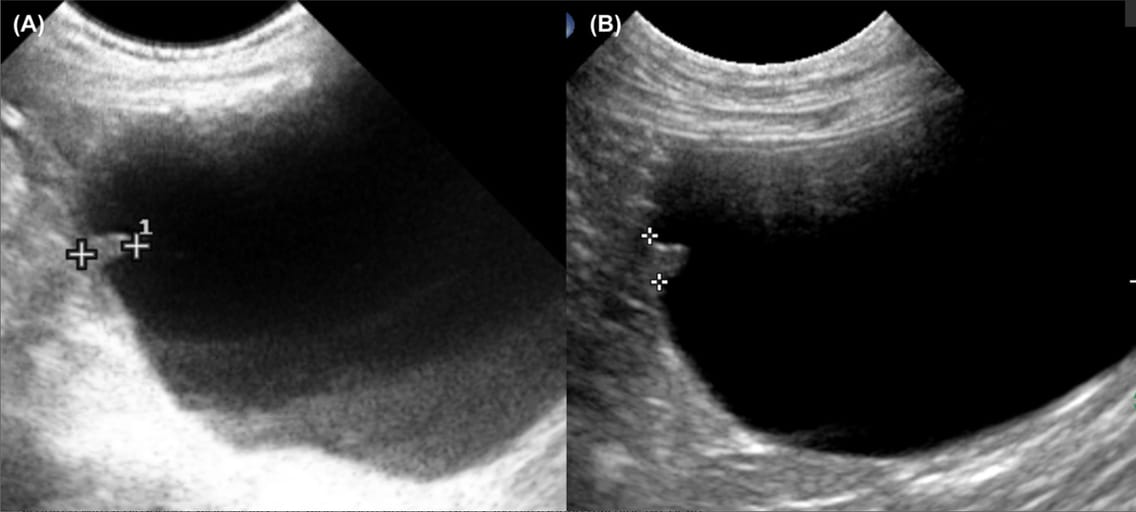

Longitudinal plane ultrasonographic images of two dogs. One small nodule was present at the apex of the urinary bladder in each dog (between the digital calipers). Note that the margins of the nodules were smooth and, they were protruding into the lumen. The apex nodules had an oblong shape (A) and triangular shape (B), respectively. For ultrasonography, the dog was placed in right lateral recumbency, the fur was clipped, and ultrasound gel was applied. B-mode ultrasound images of the urinary bladder distended with urine were acquired with a Biosound EsaoteMegas ES (Esaote North America, Fishers, IN) ultrasound machine (A), or an Aplio i800, Canon Medical Systems USA, Inc, (Tustin, California) ultrasound machine (B), and a 5–9 MHz microconvex array transducer in the longitudinal plane (A and B)

Apex nodules were identified in 6% (8/134) of Scottish Terriers. These nodules were single, well-defined, isoechoic to the bladder wall, and protruded into the lumen. Their base measured 2–4 mm, with a height of 4–6 mm. Five dogs underwent serial ultrasonographic evaluations (up to 3.5 years), with no observed changes in nodule size or morphology. Cystoscopic evaluation in three dogs revealed normal mucosal coverage, and histopathology in two dogs confirmed a benign fibrous structure with no neoplastic features. Three dogs later developed urothelial carcinoma at sites distant from the apex nodule, suggesting no direct association between the nodule and tumor development.